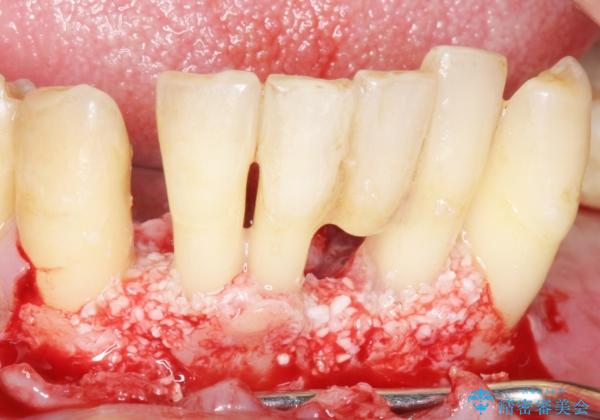

できるだけ自分の歯を残したいという患者様の強いご希望により、禁煙指導後再生療法(骨を増やす手術))を行いました。

再生療法から1年後リエントリー手術により骨の再生を確認し、骨外科処置(骨を平らにして歯周ポケットの根本的な改善を図る処置)を行ったのち、連結補綴を行いました。

再生療法と骨外科処置により、歯周ポケットは全周2mm以下に改善されました。